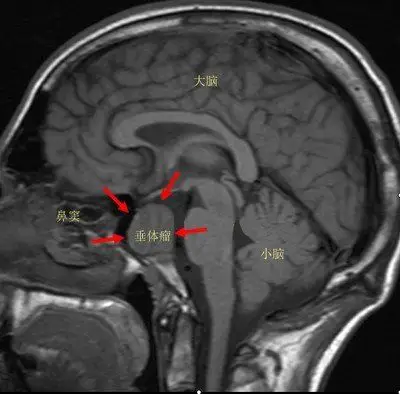

揭开垂体瘤神秘的面纱 - 好大夫在线